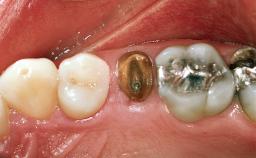

In February 2002, a 31-year-old non-smoking male patient was referred by his dentist after the fracture of the crown of the maxillary right second premolar, tooth 15. The fracture line was located apically to the gingival margin, particularly on the palatal side. Radiographic examination revealed the presence of a previous endodontic treatment with a non-ideal apical seal. There were no signs of periapical osteolysis. The level of the interproximal bone was normal. The patient’s medical history did not reveal any significant findings and he was in good general health.